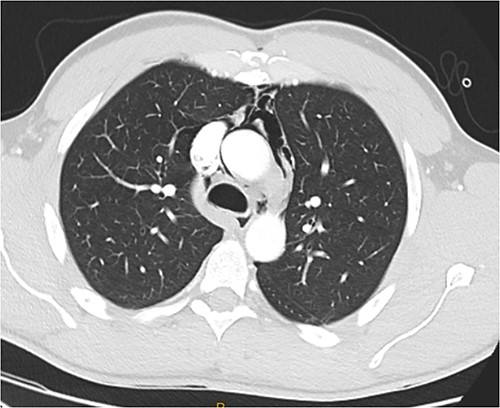

Following extubation, bilateral chest wall subcutaneous emphysema was noted extending to the neck. He also complained of central chest discomfort, without respiratory distress, oxygen desaturation or airway obstruction. Chest X-ray (CXR) revealed pneumomediastinum and surgical emphysema in the lateral chest walls bilaterally. Computed tomography (CT) of the chest, abdomen and pelvis demonstrated large volume subcutaneous emphysema bilaterally in the scrotum, abdominal and chest walls extending to the neck (see Figs 2–5). Gas was noted between the abdominal muscle layers, extraperitoneal and retroperitoneal spaces without pneumoperitoneum (see Figs 5–6). Moderate pneumomediastinum was prominent within the superior and antero-inferior mediastinum without evidence of tracheal or oesophageal injury and an associated small left pneumothorax was noted (see Figs 1–3).

CT chest axial, small left pneumothorax and chest wall subcutaneous emphysema.